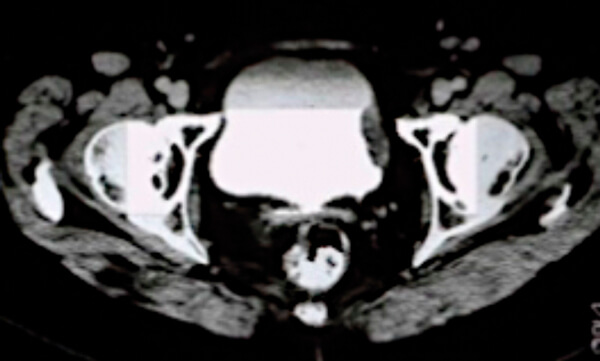

Figure 1.

- What does the scan in Figure 1 show?

1. This is a CT urogram of the pelvis demonstrating a filling defect in the bladder suspicious for muscle invasive bladder cancer. A CT chest is needed to complete the staging.